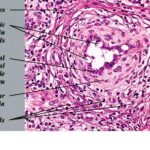

Angiolymphoid hyperplasia with eosinophilia (ALHE) shows characteristic histologic features, including a proliferation of small blood vessels, many of which are lined by enlarged endothelial cells with uniform ovoid nuclei and intracytoplasmic vacuoles. These distinctive endothelial cells have been described as having a cobblestone appearance. In addition, a perivascular and interstitial infiltrate composed primarily of lymphocytes and eosinophils (see the image below) is present. Eosinophils typically comprise 5-15% of the infiltrate. Rarely, they can account for as much as 50% of the infiltrate. Occasionally, the infiltrate is devoid of eosinophils. Lymphoid aggregates with or without follicle formation are typical.